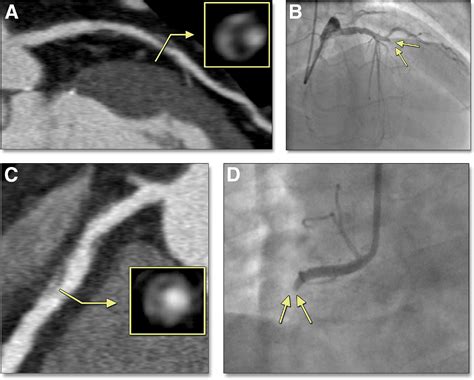

Napkin Ring Sign. It has been shown to possess a high predictive value in predicting future cardiac events and is considered one of the imaging correlates of an unstable plaque. Web the napkin ring sign may refer to either of the following imaging findings:

All procedures were performed in accordance with local and federal regulations and the declaration of helsinki. Web check out our napkin ring and sign selection for the very best in unique or custom, handmade pieces from our shops. Web the napkin ring sign may refer to either of the following imaging findings: And 2) attenuation of the ring presenting higher than those of the adjacent plaque and no >130 hounsfield units. Colonic stenosis such as due to colon cancer napkin ring sign (coronary): It has been shown to possess a high predictive value in predicting future cardiac events and is considered one of the imaging correlates of an unstable plaque. Web the apple core sign, also known as the napkin ring sign (bowel), is most frequently associated with constriction of the lumen of the colon by a stenosing annular colorectal carcinoma. 1) the presence of a ring of high attenuation around certain coronary artery plaques;